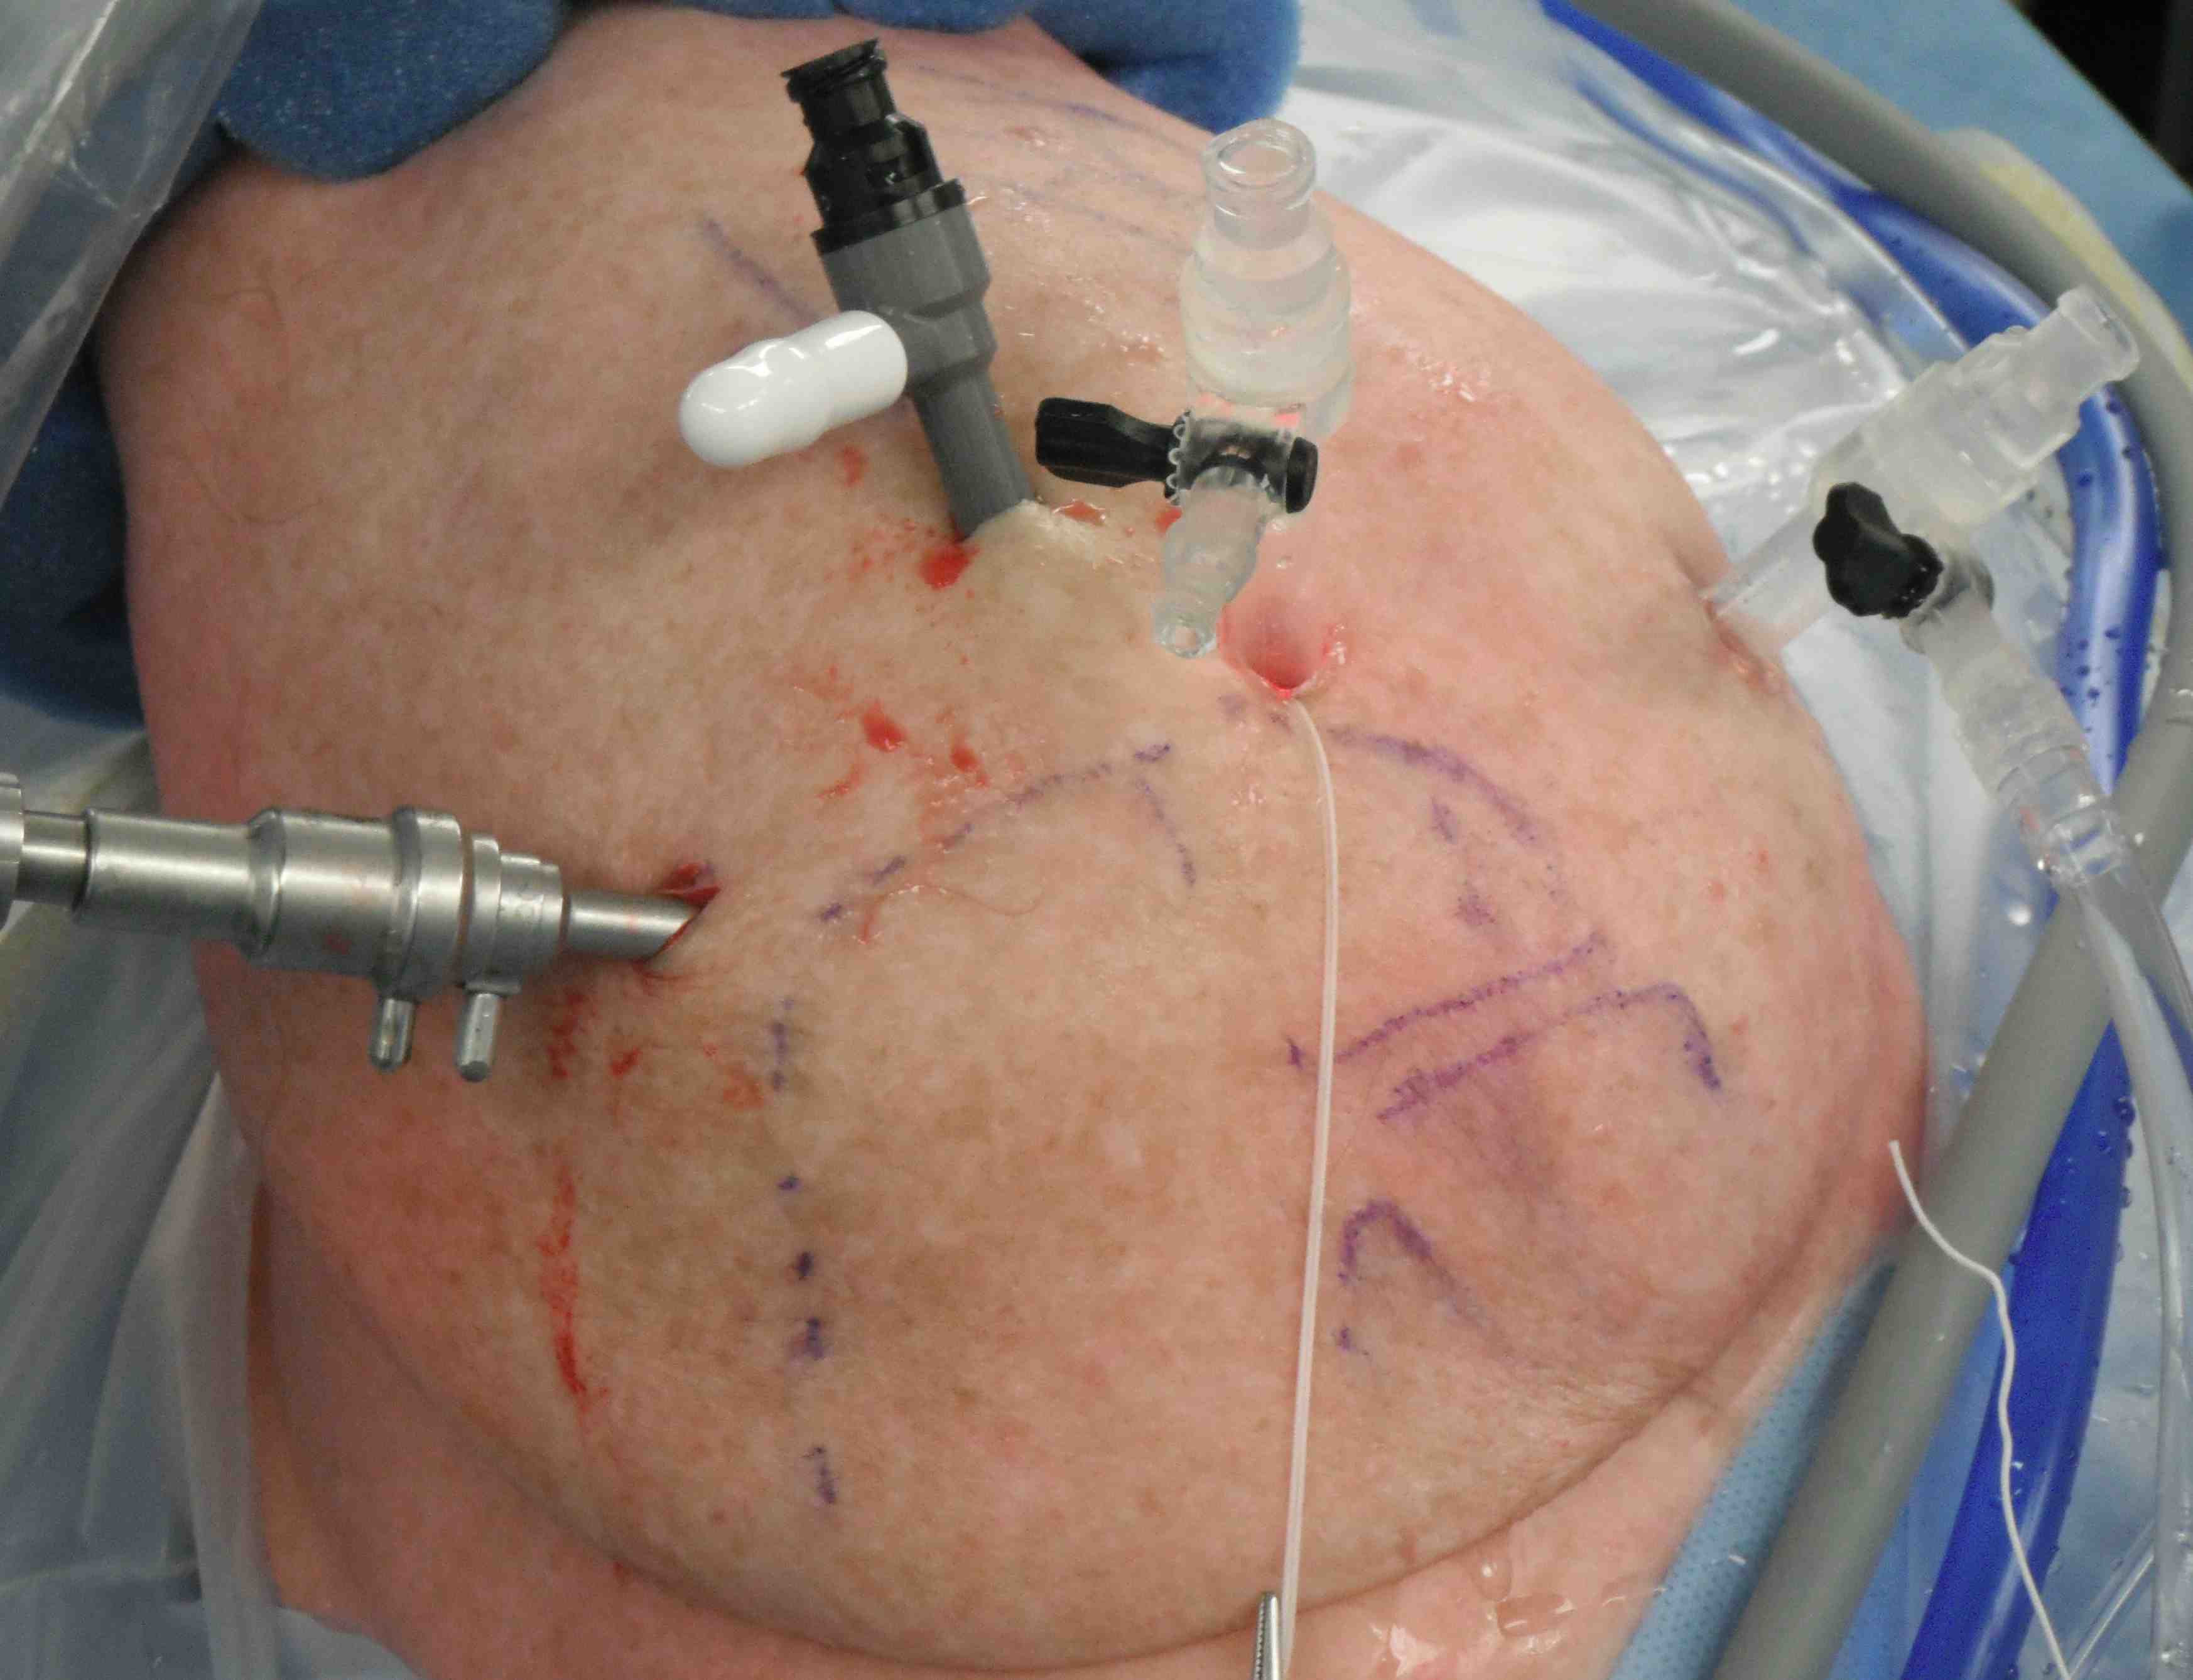

Portals

- posterior portal very lateral so can see anterior aspect subacromial space

- port of Wilminton at anterolateral acromion to access SSC

- anterior portal in normal position, slightly more lateral so becomes working portal

- place standard lateral portal as well